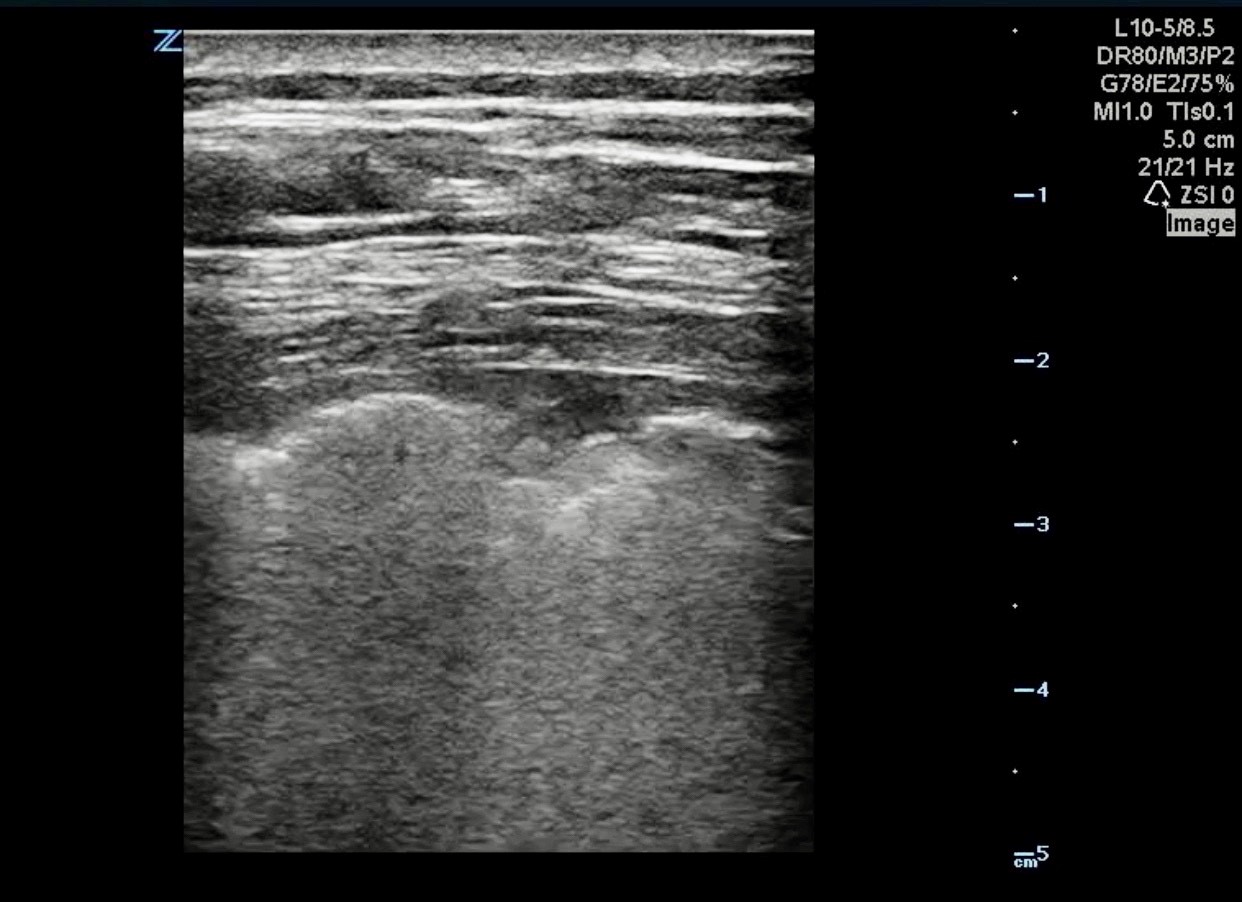

To obtain the best image quality for the assessment of COVID-19 lung pathology, it is recommended that a high frequency linear array probe or a curvilinear probe be used.3-5 The typical lung ultrasound pathology described in patients with COVID-19 are as follows:3,5,6

- Fused B lines and are visible under the pleura. B lines can appear discrete, multifocal, or confluent.

- The involved interstitial tissues have localized thickening and edema, and there is localized pleural effusion around the lesions.

- The pleural line is discontinuous, interrupted, and not smooth.

- Subpleural lesions demonstrate patchy, and nodular consolidation.

- Air bronchogram sign or air bronchiologram sign can be seen in the consolidation.

[Image displaying points 1 and 3]